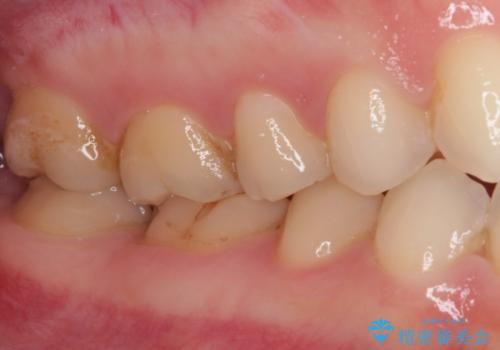

- 奥歯の銀歯をセラミックにしたいとのことで来院された患者様です。

より白さが目立つように、自然な仕上がりではなく、作り物の雰囲気があるフルジルコニアクラウンにて補綴治療を行いました。